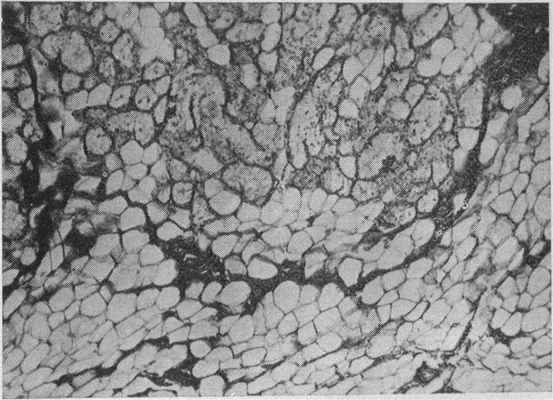

С увеличением сроков пользования протезами (более 4 лет) в кости твердого неба и альвеолярного отростка отмечаются более глубокие гистоструктурные изменения (рис. 46, а, б). Они в равной степени наблюдаются во всех возрастных группах. Наиболее выраженные изменения наблюдаются в кортикальном слое кости альвеолярного отростка, в котором происходит образование лакун различной формы и размера, выполненных рыхлой соединительной тканыо с большим количеством остеобластов и тонкостенных капилляров. Нередко на месте исчезнувшей кости остается плотноволокнистая ткань, сохраняющая частично конфигурацию бывшей кости. Такое состояние кости, по мнению Е. Frolich (1952), является выражением приспособительной реакции.

Рис. 46. Кость альвеолярного отростка. Мужчина 77 лет, срок пользования протезом 3 года, а — лакунарное рассасывание кости альвеолярного отростка со скоплением остеокластов. Окраска гематоксилин-эозином. Х400; б — резорбция костной балки остеокластами (1). Слева в углу полости (2) располагается остоидная зона, по краям которой расположены остеобласты. На месте исчезнувшей кости — соединительная ткань. Женщина 67 лет, срок пользования протезом 3 года. Окраска гематоксилин-эозином. Х80 (Дуйшалиев К. Д.)-

При длительном сроке пользования протезами (более 8 лет) процессы резорбции кости замедляются. При этом на месте бывших лакун рассасывания появляются незначительные остеоидные зоны. Такие картины также подмечены F. Singer, Н. Мегап (1961) и заставляют думать о том, что появление остеоидных зон в более поздние сроки пользования протезами отражает физиологическую перестройку кости в результате наступившего равновесия.

Таким образом, морфологические исследования показали, что ткани протезного ложа беззубой верхней челюсти отвечают определенной реакцией на те необычные условия, в которых они оказываются под базисом пластиночного протеза. При пользовании протезами до 3 лет надкостница альвеолярного отростка утолщается. Но с увеличением сроков пользования протезами она, наоборот, истончается, превращаясь в плотный слой фиброзной ткани. Остеобласты камбиального слоя исчезают. В кости твердого неба и альвеолярного отростка после 3-летнего пользования протезами отмечается выраженная резорбция за счет остеокластов, дистрофические изменения и понижение регенераторной потенции кости. Костные балки значительно истончаются, обычная архитектоника нарушается. Костномозговые полости заметно расширяются. Костный мозг замещается жировой и фиброзной тканью. Определенные морфологические изменения претерпевают также сосуды и нервы слизистой оболочки, надкостницы и костного мозга.